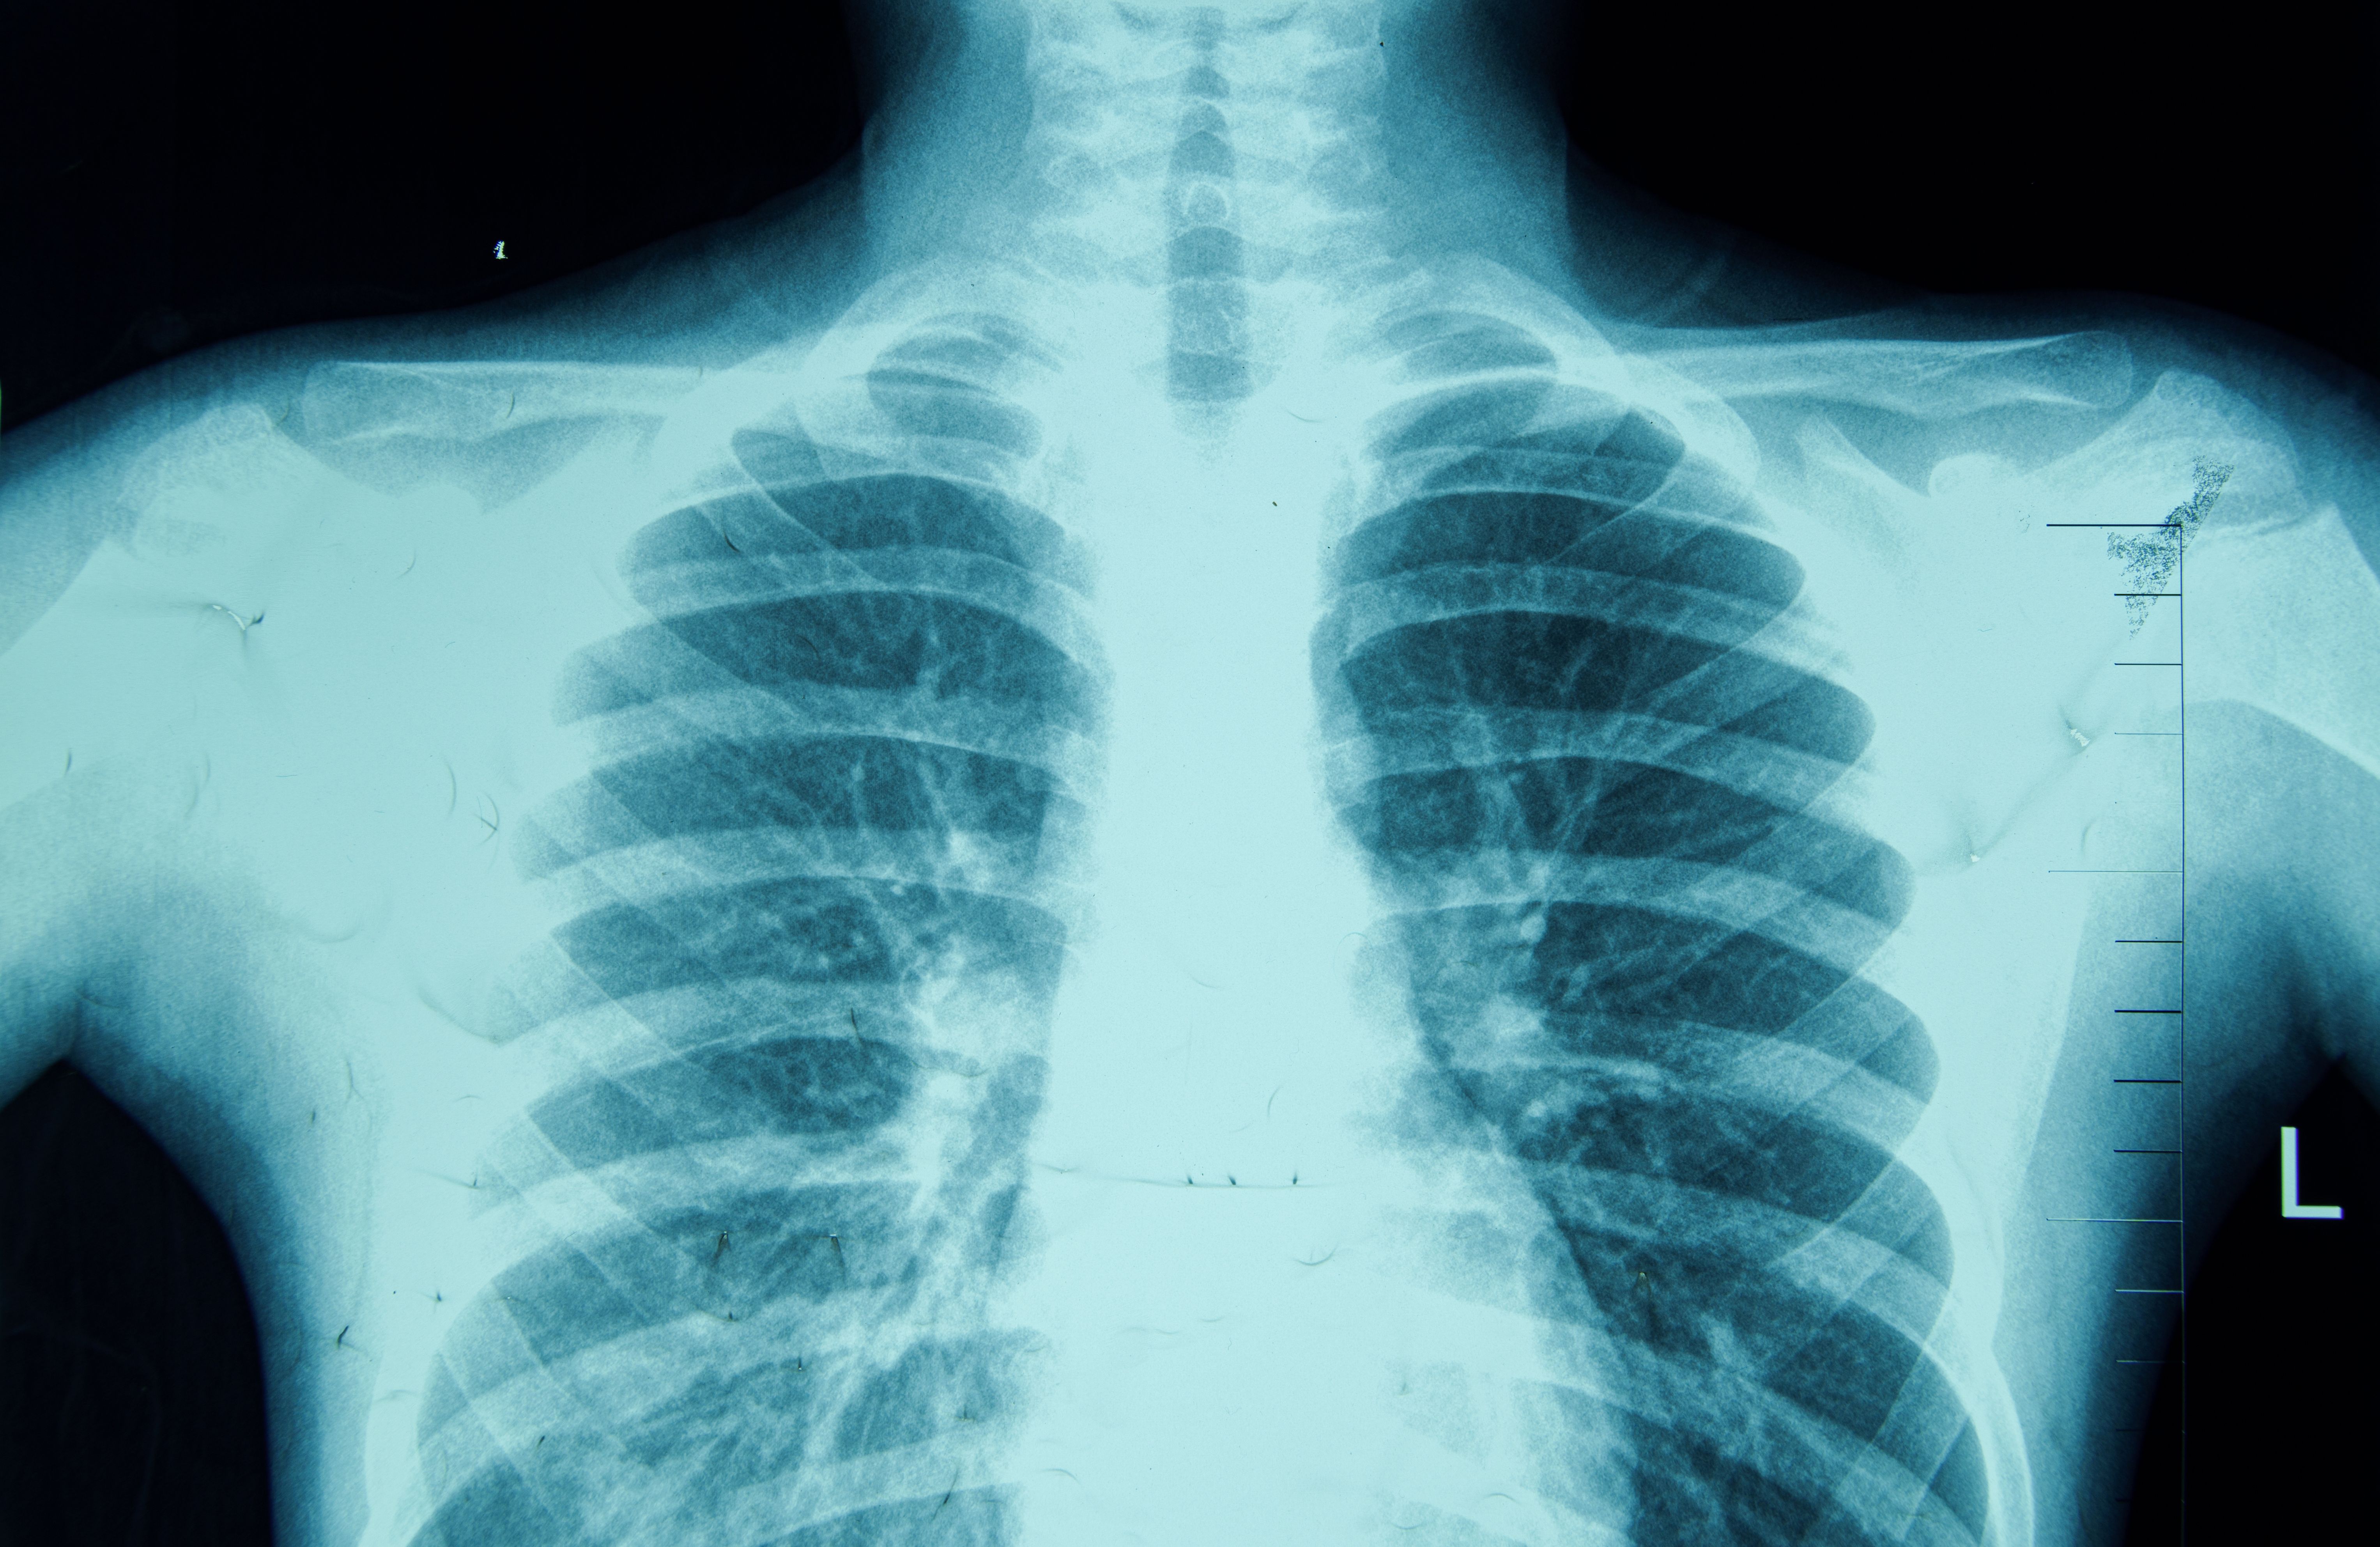

Artificial intelligence is enhancing diagnostic accuracy by providing medical professionals with advanced tools that assist in interpreting medical images such as X-rays, MRIs, and CT scans. These AI-powered tools can identify anomalies and suggest potential diagnoses, often with higher accuracy than traditional methods. This not only speeds up the diagnostic process but also reduces the likelihood of human error.

Moreover, AI algorithms are continuously learning and improving from new data, which means their diagnostic capabilities are constantly evolving. This ensures that patients receive the most accurate and up-to-date information regarding their health conditions.